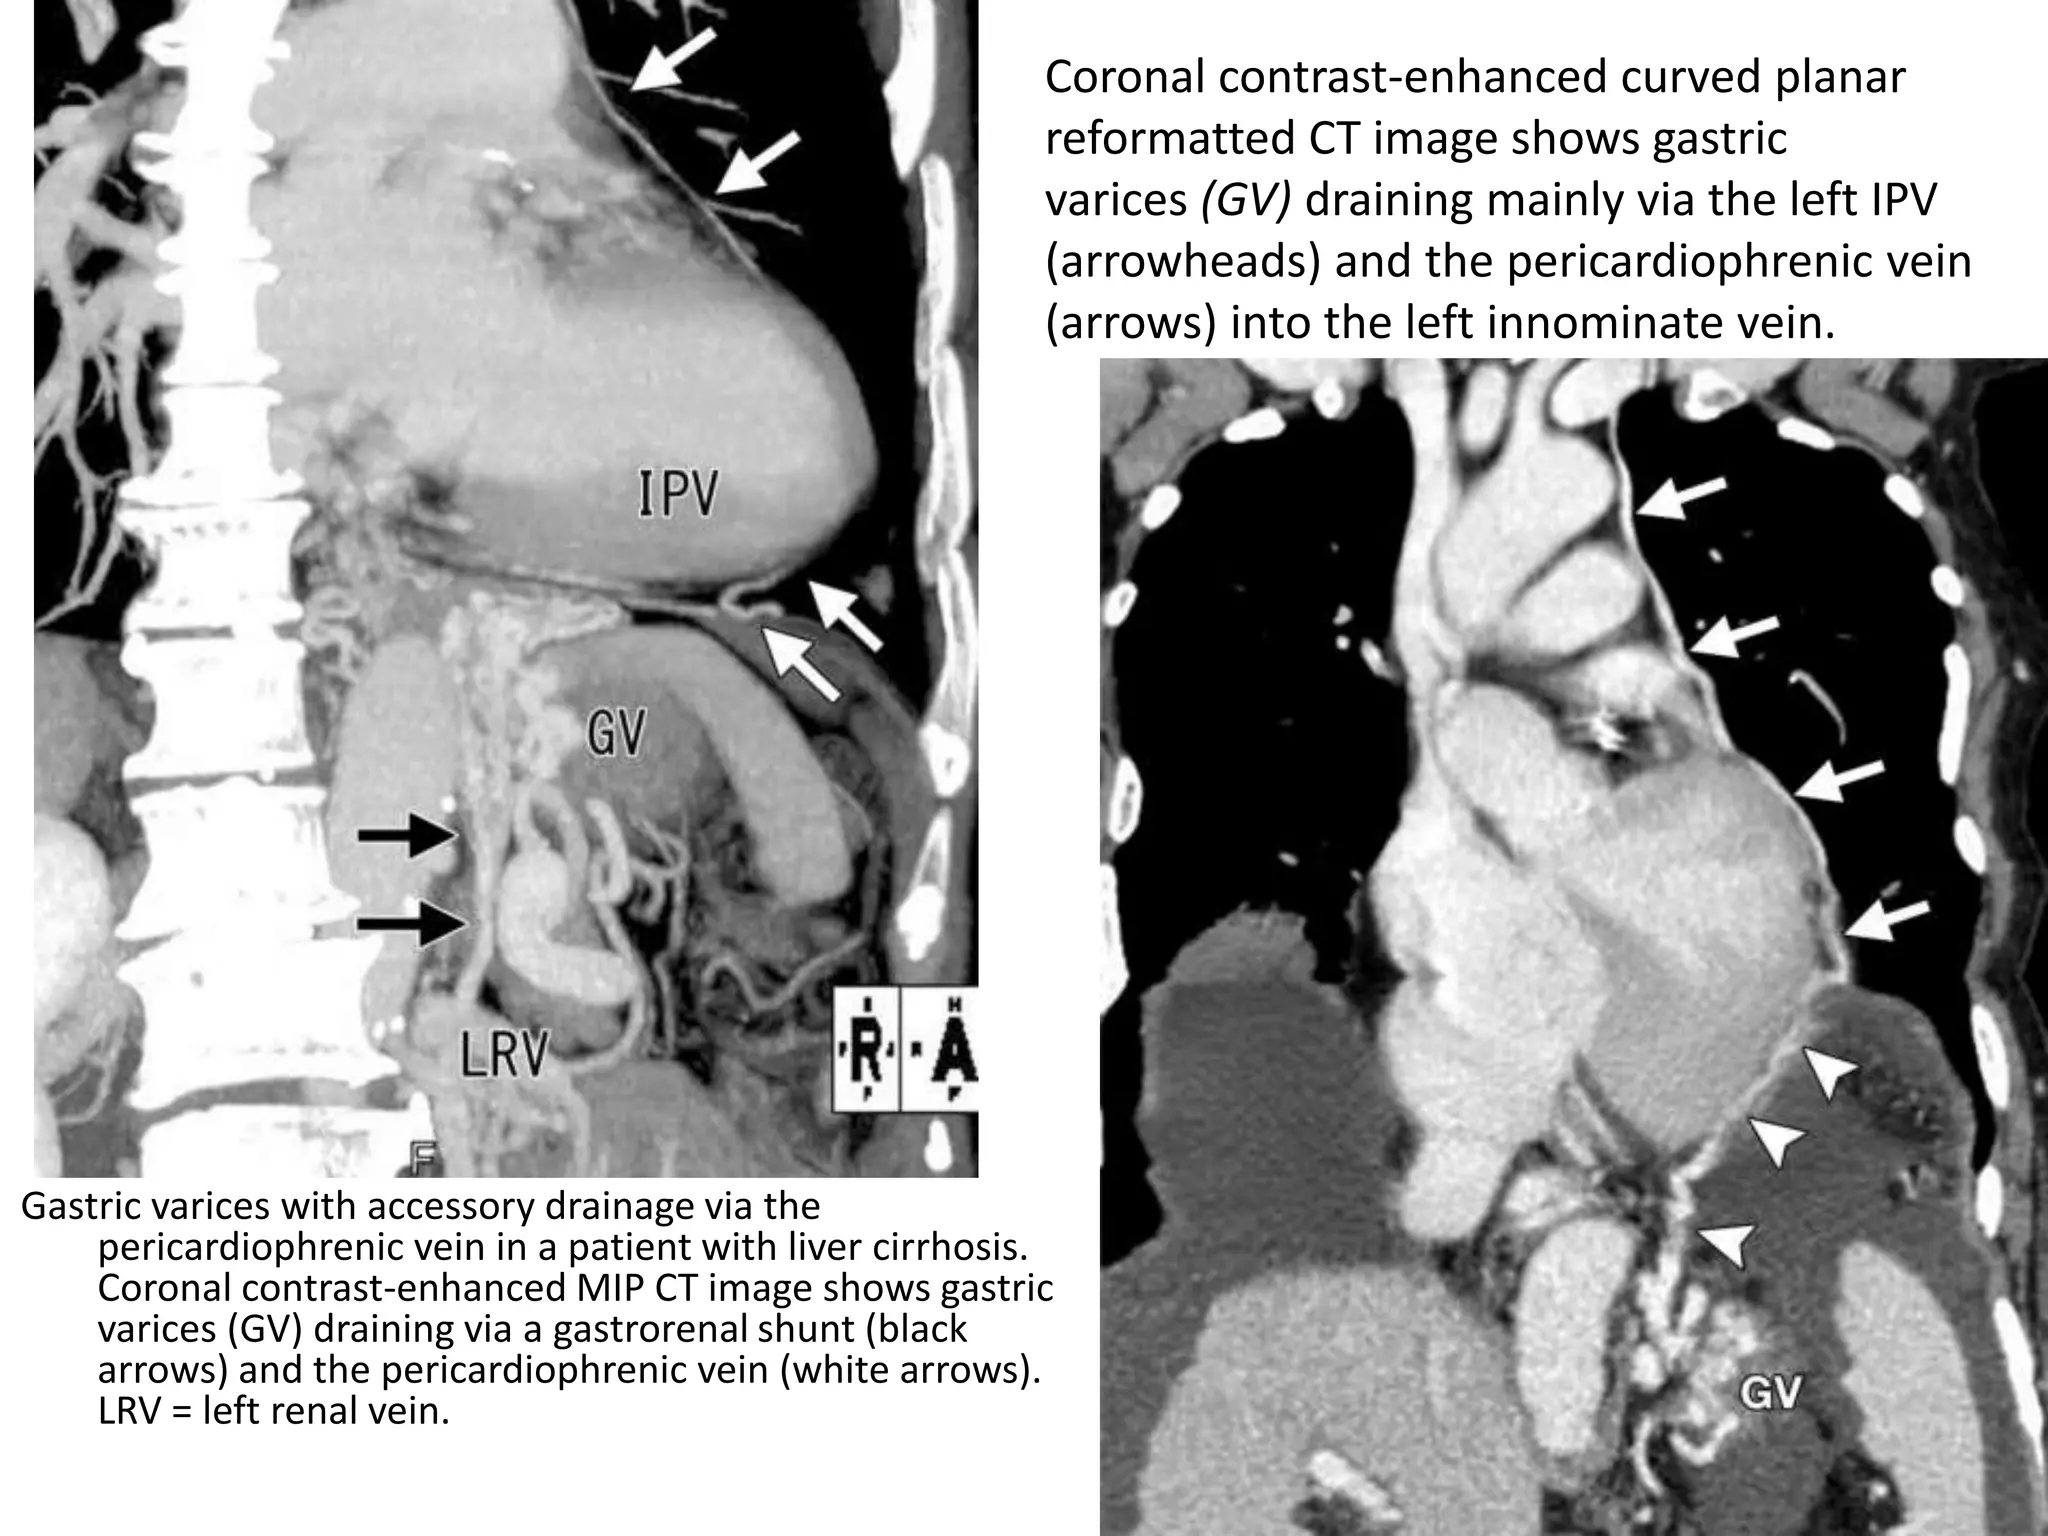

Gastric varices with accessory drainage via the

pericardiophrenic vein in a patient with liver cirrhosis.

Coronal contrast-enhanced MIP CT image shows gastric

varices (GV) draining via a gastrorenal shunt (black

arrows) and the pericardiophrenic vein (white arrows).

LRV = left renal vein.

Coronal contrast-enhanced curved planar

reformatted CT image shows gastric

varices (GV) draining mainly via the left IPV

(arrowheads) and the pericardiophrenic vein

(arrows) into the left innominate vein.